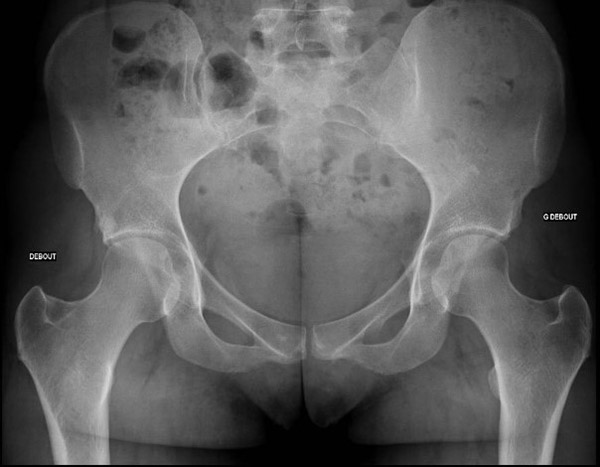

Standard - X-rays

Standard – x-rays

• ✔️ Femoro acetabular impingement Pincer type By TRUE acetabular retroversion (acetabular posterior dysplasia)

3 signs: cross-over sign, ischial spine sign, posterior wall sign

Retroversion index > 30%

Femoro acetabular impingement Pincer type By TRUE acetabular retroversion